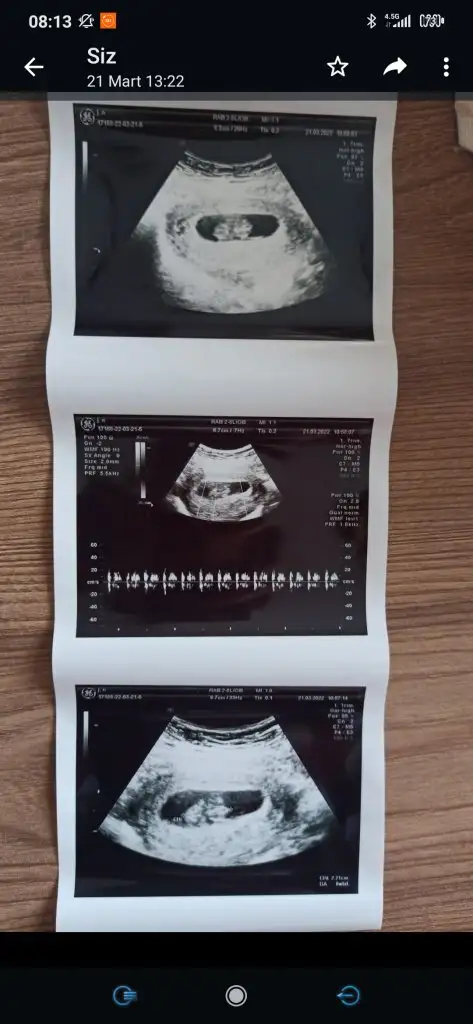

Nurcum bunada yorum yapabilir misin cinsiyeti ne ?y

yorumladıklarıma hep uğurlu geliyorum galiba kızlarerkek gibi duruyor kuzum plesanta maşallah

kesen çok güzel maşallahNurcum bunada yorum yapabilir misin cinsiyeti ne ?

kuzum buda kız gibi duruyorEki Görüntüle 3033276